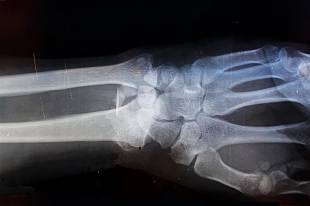

이러한 상태는 X-ray에서 아주 얇은 금처럼 보일 때가 많으며, 부기가 서서히 증가하면서 해당 부위에 열감이 퍼집니다. 환자는 이를 단순 타박상으로 생각하기 쉬우나, 압력을 가할 때 내부에서 당김과 쿡쿡 찌르는 느낌이 반복되는 경우 골절의 가능성이 높습니다. 특히 손가락이나 발가락처럼 작은 뼈는 미세 골절이 있어도 움직임이 제한되지 않는 것처럼 보여 오해하기 쉽습니다.

뼈의 일부가 실제로 분리되기 시작한 상태란 외부 충격이나 반복적인 스트레스로 인해 뼈가 지탱 능력을 일부 상실한 경우 발생합니다. 예를 들어 자전거에서 넘어지면서 손을 바닥에 짚는 순간이나, 계단 모서리에 강하게 부딪히는 사고가 여기에 해당합니다. 이때 골절이란 통증이 전기처럼 순간적으로 번지며, 부위가 빠르게 붓고 온도가 올라가는 양상이 관찰됩니다.